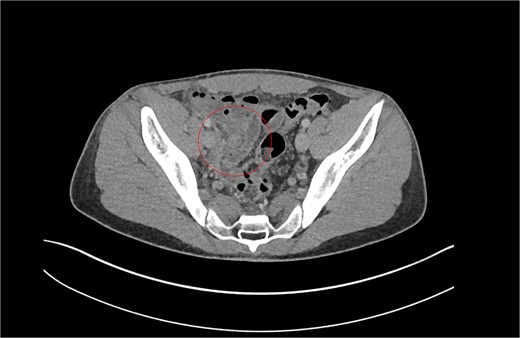

Patient A. Appendiceal stump of Patient A identified within the red circle on CT scan before the second operation.

Having had a previous appendicectomy with for perforated acute appendicitis with a postoperative collection, the differential diagnoses raised on CT KUB were either a stump appendicitis or a terminal ileitis. The patient was commenced on IV co-amoxiclav and formal contrast enhanced computer tomography of the chest, abdomen, and pelvis (CT CAP) was organized, revealing a residual long appendiceal stump infection associated with a small localized collection and caecal thickening.

Review of previous notes revealed that the patient had a laparoscopic appendicectomy 2 years prior from a CT-confirmed acute retrocaecal appendicitis with localized perforation at the tip (Fig. 1). Intraoperatively, the dissection proved difficult due to the presence on multiple inflammatory adhesions and the retrocaecal position of the appendix, however a retrograde appendicectomy was completed laparoscopically. The postoperative period was complicated by a right iliac fossa abscess that was successfully treated with IV antibiotics and CT-guided drainage. The index histology revealed multiple pieces of appendiceal tissue aggregating to 60 mm × 40 mm × 20 mm, with acute inflammation and necrosis.